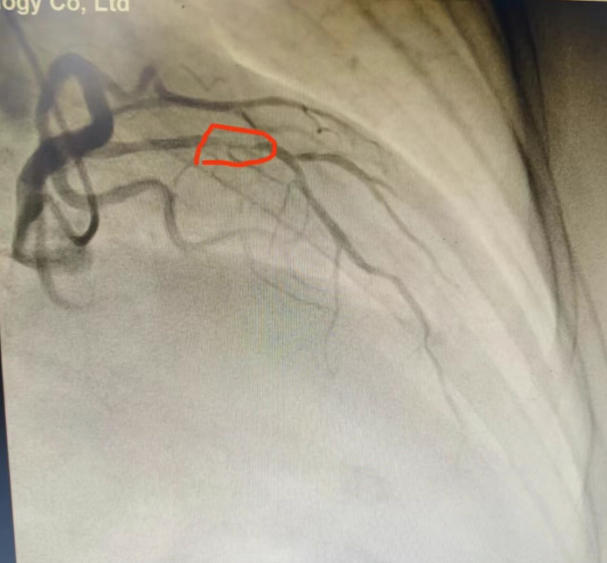

"若不打通堵塞的血管,心衰随时会复发。"心内二科马东亮主任判断患者心脏最重要的血管前降支存在严重狭窄。经与家属深入沟通,导管室团队为患者实施冠脉造影,结果证实前降支近段堵塞超过90%。通过微创介入药物球囊扩张成形术,团队成功开通病变血管,术后患者心脏功能得到根本改善。

术前